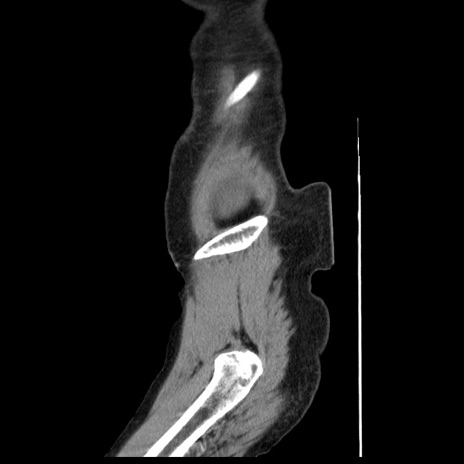

症例1(矢状断像)

【症例】80歳代女性

【主訴】腹痛

【現病歴】8時間前から腹痛あり来院。

【既往歴】糖尿病、脂質異常症、子宮体癌にて子宮全摘術

【身体所見】意識清明・会話良好だが腹痛で苦悶様、全腹部にわたって反跳痛と圧痛あり

【データ】WBC 13600、CRP 0.14、LDH 224、CK 90